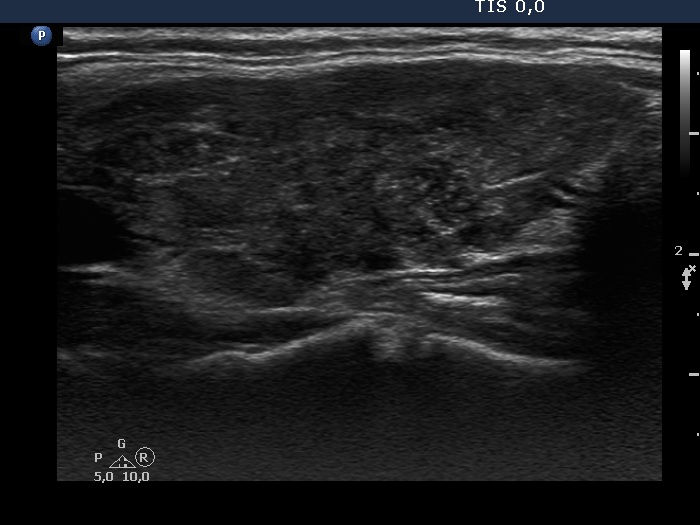

Consecutive patients with the final diagnosis of Hashimoto's thyroiditis - case 28 (481) (ultrasonographic picture 6)

Left lobe, longitudinal scan.